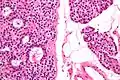

Micrographs